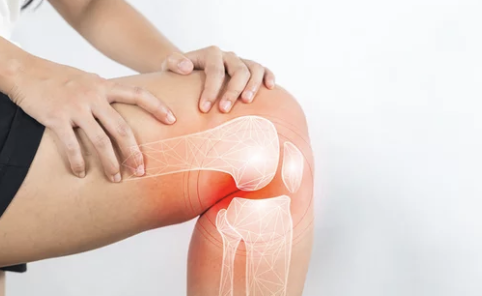

무릎 인공관절 수술은 퇴행성 관절염이나 연골 손상으로 인해 무릎 통증이 심각해져 일상생활이 어려운 사람들에게 매우 유용한 치료법입니다. 이 수술은 통증을 줄이고, 무릎의 기능을 회복하는 데 도움을 줄 수 있습니다. 하지만 많은 사람들이 수술비용에 대해 걱정하며, 이 수술에 대해 구체적으로 알아보기를 원합니다. 이번 글에서는 무릎 인공관절 수술비용에 대해 자세히 알아보고, 수술비 절감 방법 및 주의해야 할 점들을 설명하겠습니다. 🏥💡

무릎 인공관절 수술은 손상된 무릎 관절을 제거하고, 이를 대신할 인공관절을 삽입하는 수술입니다. 주로 퇴행성 관절염, 연골 손상, 또는 무릎 관절의 기형으로 인해 무릎 기능이 심각하게 손상된 사람들에게 시행됩니다.

- 퇴행성 관절염: 무릎 연골이 닳아 통증이 심해지며, 걷거나 일상적인 활동이 어려워질 때.

- 관절 손상: 무릎 관절의 연골이 손상되어 복구할 수 없을 때.

- 관절 기형: 관절의 구조적 문제로 인해 무릎 통증이 생기고, 변형된 무릎이 일상생활을 방해할 때.

무릎 인공관절 수술은 통증을 완화하고, 운동 범위와 활동성을 회복시켜 일상생활을 보다 편리하게 만들어줍니다. 하지만 수술비용이 만만치 않기 때문에 많은 사람들이 수술 전 비용을 걱정하게 됩니다.